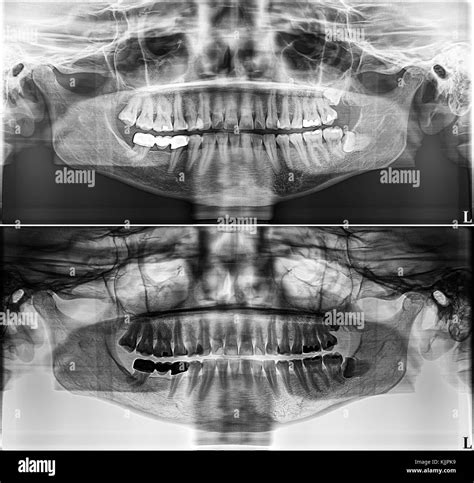

The primary advantage of a panoramic X-ray is the sheer volume of information it provides in a single image. While localized dental X-rays are excellent for detecting small cavities between teeth, they often miss larger issues hiding deep within the jaw or under the gumline. A panoramic Xray teeth image serves as a baseline for your dental history and is often the first step in creating a long-term treatment plan.

• Orthodontic Planning: It allows orthodontists to see the position of all teeth, including those that have not yet erupted, such as wisdom teeth.

• Jaw Health: It is instrumental in identifying issues with the TMJ, which can cause chronic headaches and jaw pain.

• Disease Detection: The scan helps visualize cysts, tumors, abscesses, or infections within the jawbone that might be asymptomatic.

• Implant Planning: Surgeons use the detailed view to assess bone density and height before placing dental implants.

• Trauma Assessment: If a patient has suffered a facial injury, the panoramic view helps identify fractures in the mandible or maxilla.